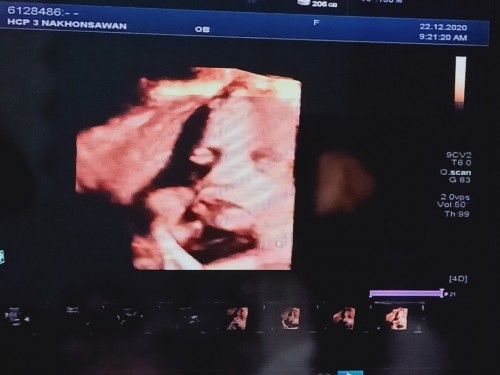

ลูกชายคร้า